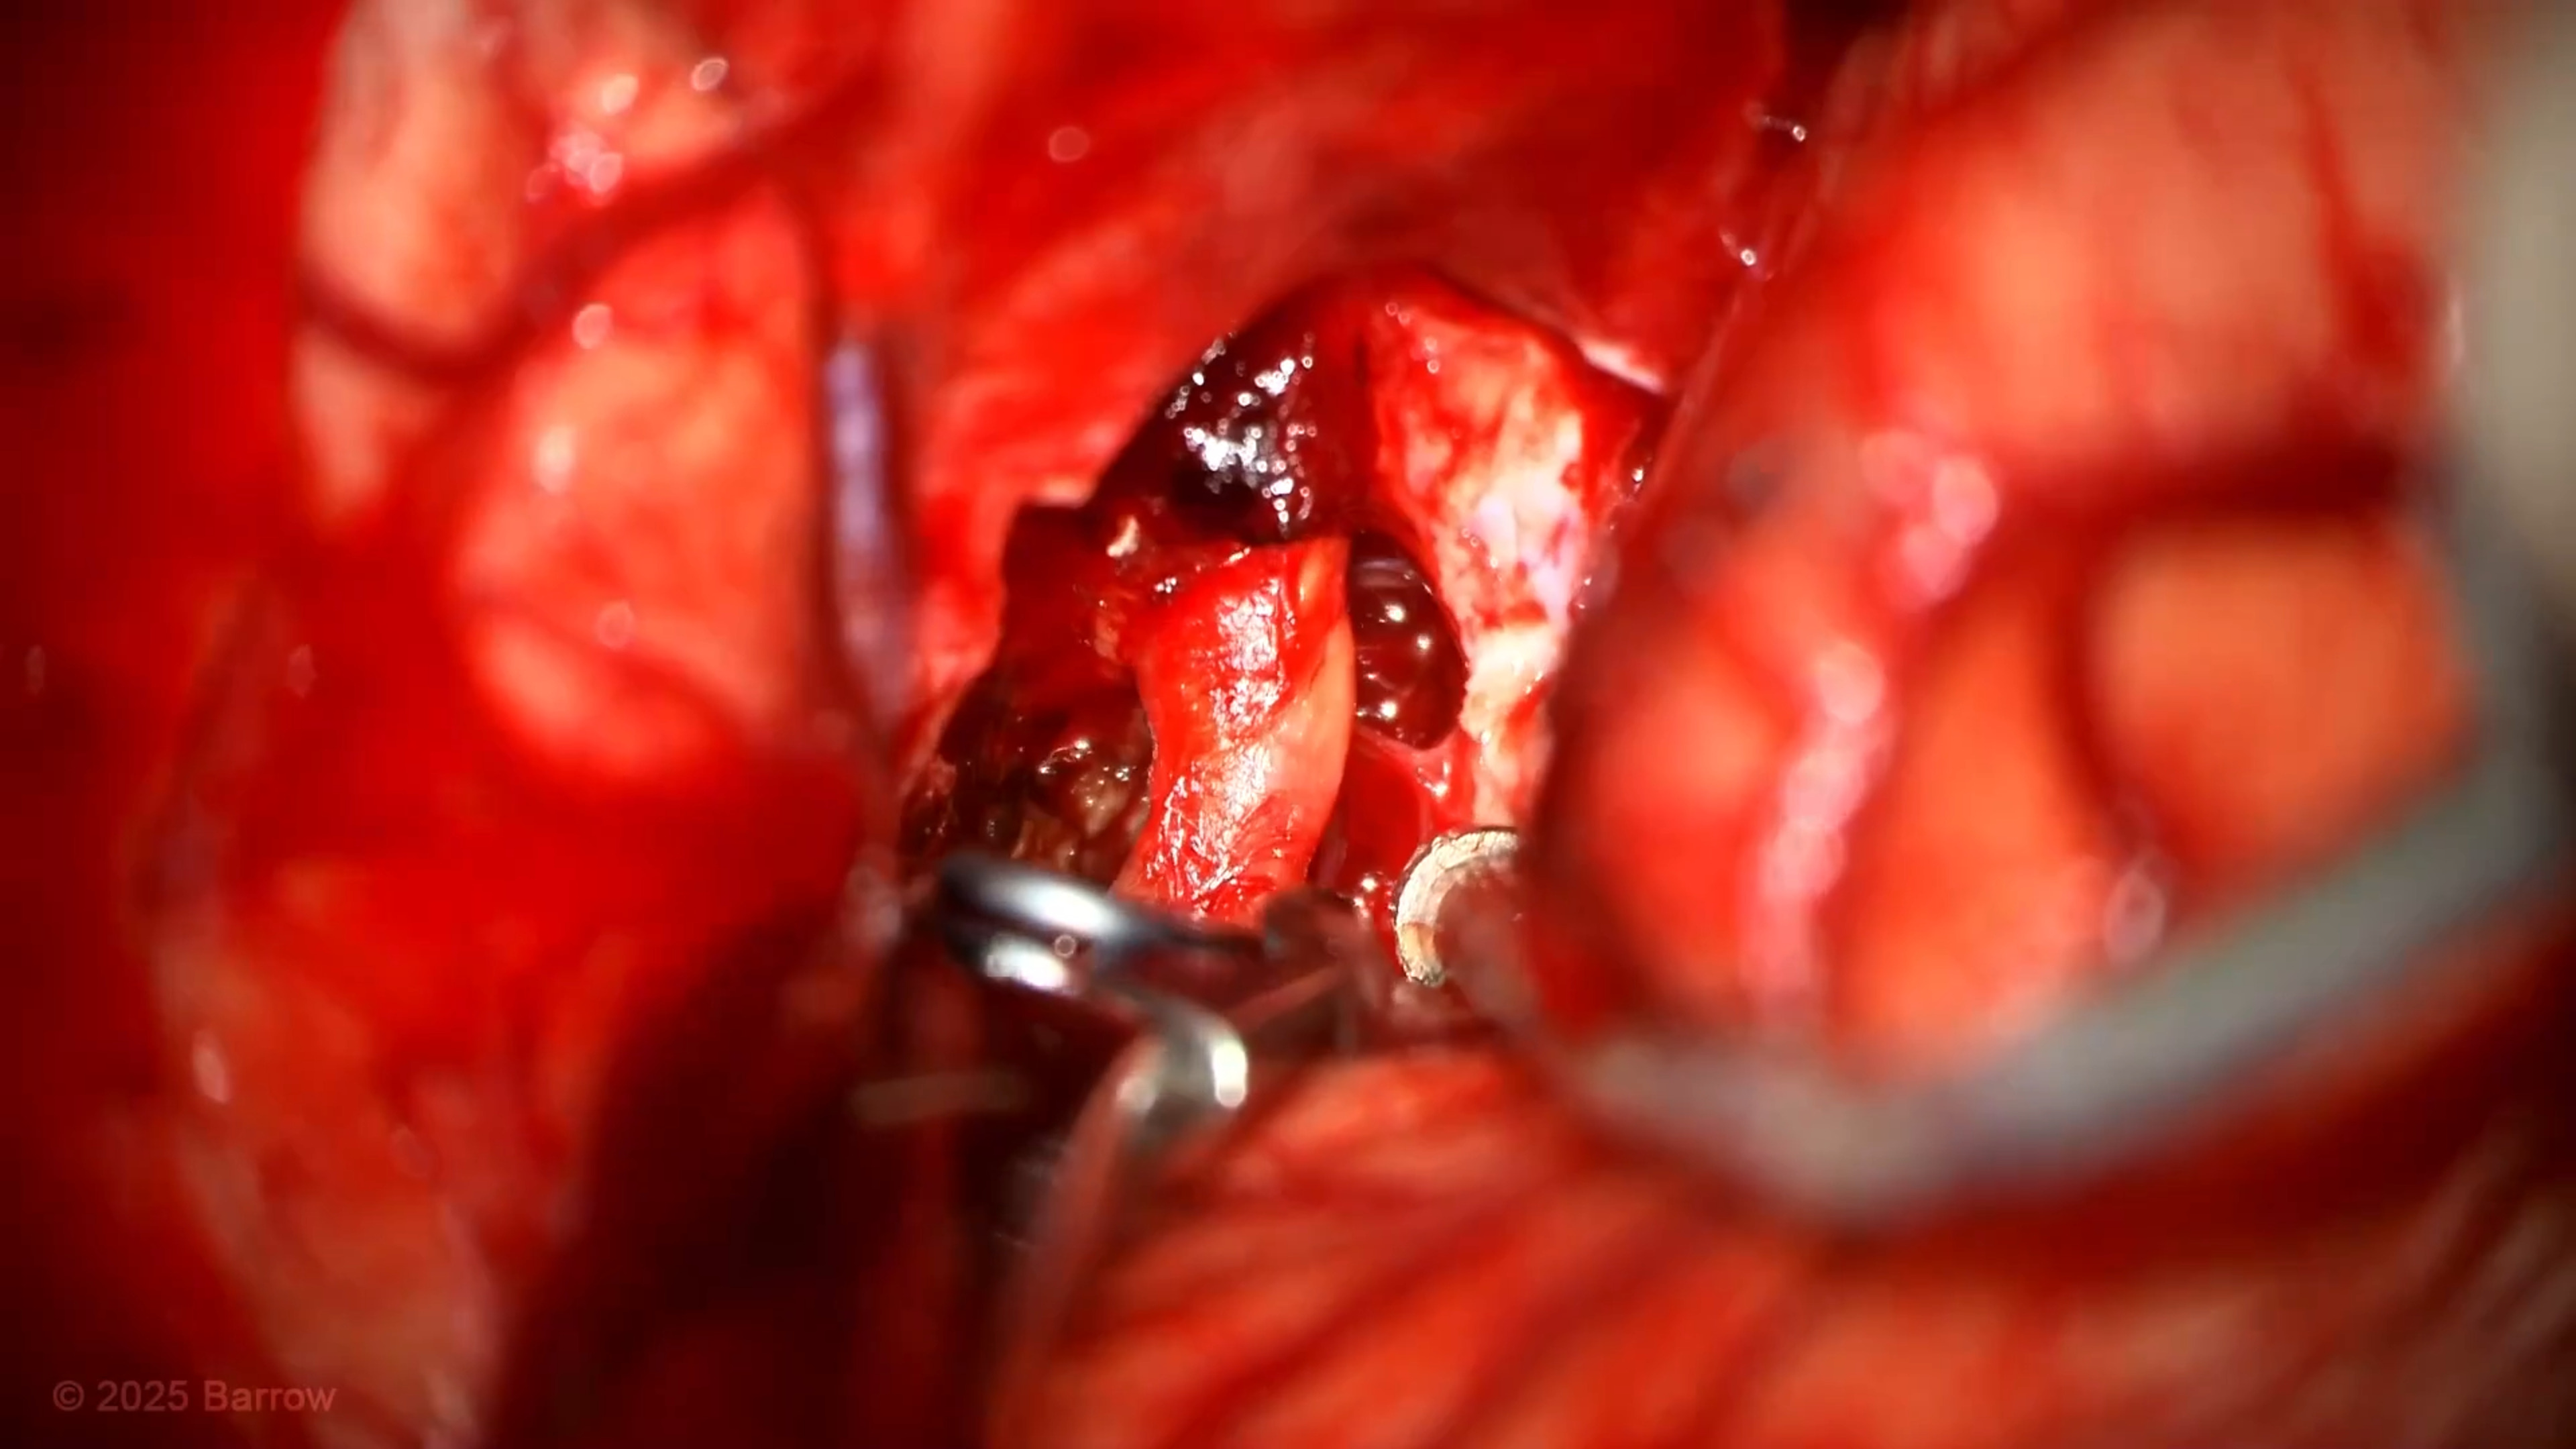

#503: Minipterional Craniotomy for Clipping of a Calcified Middle Cerebral Artery Aneurysm

Episode 503 of Seven Series shows a minipterional craniotomy for clipping of a calcified middle cerebral artery aneurysm.